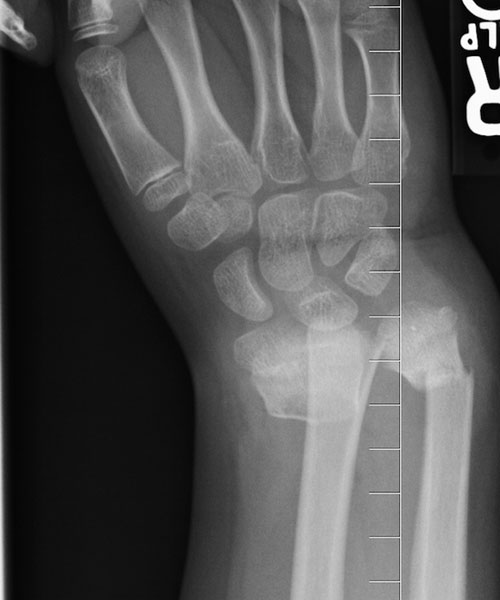

CAMERON’S BROKEN WRIST

Trampoline accident • July 30, 2011 • 4 x-rays